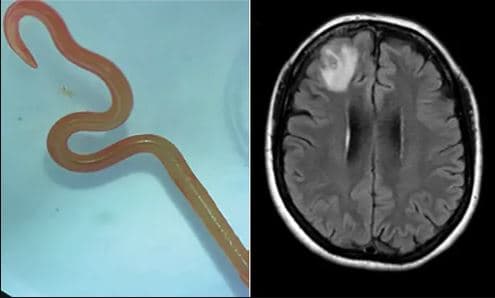

Σκουλήκι 8 εκατοστών αφαιρέθηκε από τον εγκέφαλο γυναίκας

Για πρώτη φορά στα χρονικά της ιατρικής, ένα σκουλήκι που κανονικά παρασιτεί σε πύθωνες αφαιρέθηκε ζωντανό από τον εγκέφαλο μιας άτυχης γυναίκας στην Αυστραλία.

Το παράσιτο, του είδους Ophidascaris robertsi, ανήκει στην ομάδα των ασκαρίδων, σκουληκιών που ζουν στο πεπτικό σύστημα πολλών σπονδυλωτών ζώων συμπεριλαμβανομένου του ανθρώπου.

όμως είχαν εμφανιστεί νέα, όπως δυσκολία στη μνήμη και κατάθλιψη. Η μαγνητική τομογραφία αποκάλυψε τότε μια περίεργη κηλίδα στον δεξιό μετωπικό λοβό του εγκεφάλου.

Όταν οι γιατροί κατάλαβαν ότι επρόκειτο για παράσιτο, το αφαίρεσαν στο χειρουργείο και το έστειλαν σε παρασιτολόγους, οι οποίοι ταυτοποίησαν το είδος του σκουληκιού με μοριακά τεστ και μορφολογικές εξετάσεις.